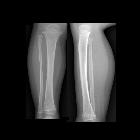

A toddler fracture is a minimally or undisplaced spiral fracture, usually of the tibia, typically encountered in toddlers. It is a potentially difficult diagnosis to establish on account of both the symptoms and imaging findings being subtle.

Conventional radiographs are all that are required, however, multiple views may be necessary as the fracture is often inapparent on one or more views. Internal oblique projection can better demonstrate the fracture in some cases . Nondisplaced oblique fracture will be noted in the middle or distal diaphysis of the tibia .

If despite multiple views, no fracture can be identified, follow-up radiographs usually will demonstrate slight sclerosis and periosteal reaction.